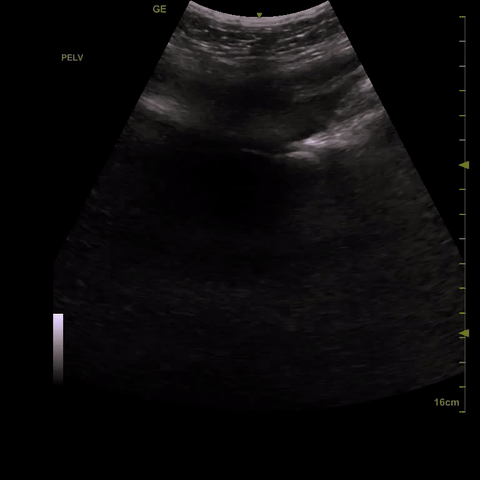

Pelvis: In the midline below the abdominal fold but superior to the pubic symphisis begin with the probe in transverse. Fan posterior to anterior through the bladder. In males pay particular attention to the rectovesical pouch and in females to the rectovaginal space (pouch of Douglas). Also look at the bladder edges for angular anechoic regions indicating fluid settling around the bladder and bowel.

Movement of free fluid: In the supine patient the pelvis is the most dependent part of the body and is the first place for free fluid to collect. However, the pelvis has a relatively small volume and quickly fills then moving to the right upper quadrant. The LUQ is the least dependent part of the abdomen. In cases free fluid originating in the LUQ, it flows following the splenocolic ligament preferentially to the RUQ.